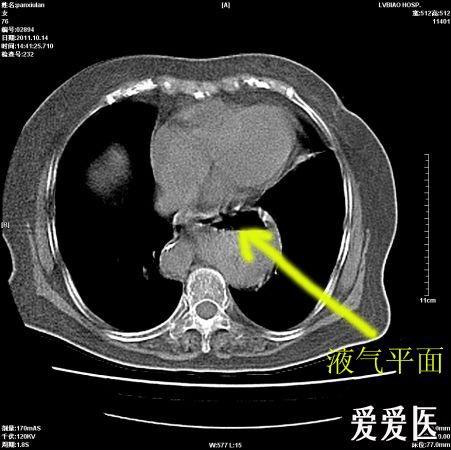

请大家分析一下左侧胃泡区液平,该片存在哪些问题 2.